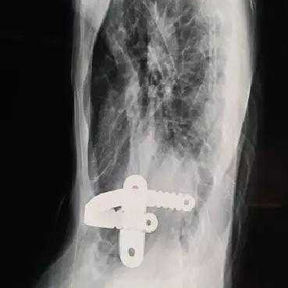

We developed a personalized surgical plan for the patient. The operation first involved making incisions along the surgical scars on both sides of the chest wall to remove the bar inserted during the Nuss procedure. Then, a larger incision was made at the central scar on the anterior chest wall to fully expose the bone structure located at concave and convex areas of the chest wall. It was found that there were severe adhesions between the chest wall structure and the pericardium, with the heart being compressed into the left chest cavity.

​First, the adhesions were thoroughly released, and a portion of the protruding ribs and costal cartilage at the top of the protrusion was cut off. By lifting and pressing down, the chest wall was adjusted to its normal height. Second, three MatrixRIBs was used to replace the removed rib sections, and their curvature was carefully adjusted to closely resemble the normal curvature of the chest wall, thereby completing the reconstruction of the thoracic cage. Third, a bar was placed and flipped within the chest wall to elevate the most depressed part of the central chest wall. Lastly, two bars were placed on and secured to the bone surface of the lower half of the chest wall. The surgery achieved a satisfactory result, eliminating the deformities and restoring the chest wall to its normal shape.